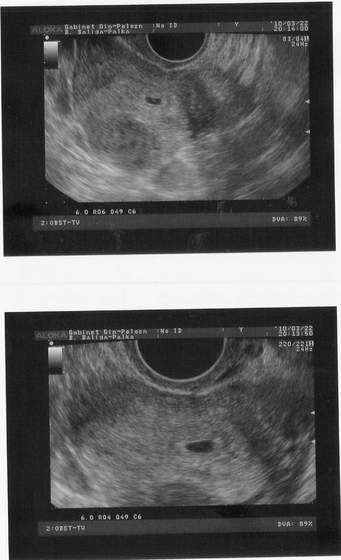

Byłam, ale nikt tego nie zauważył to się nie narzucałam. U mnie już OK. Od tygodnia nie męczą mnie już tak strasznie mdłości i mogę się cieszyć ciążą.

No dokładnie. Mój brzuchol już się zaokrąglił a to dopiero 11 tydz. W pierwszej ciąży taki jak mam teraz miałam w 5 m-cu.